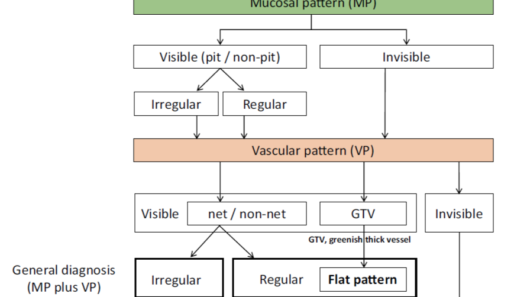

Magnifying Endoscopy Simple Diagnostic Algorithm for Gastric Cancer (MESDA-G)

Background

Since magnifying endoscopy (ME) has become common practice, numerous classifications and diagnostic systems have been proposed. To propose a unified algorithm for general use in clinical settings, the Japanese Gastroenterological Association established a working group and proposed that the Japan Gastroenterological Endoscopy Society, the Japanese Gastric Cancer Association, and the World Endoscopy Organization jointly devise a unified international algorithm for ME diagnosis of EGC based on an evidence-based approach.

Methods and Algorithm

The working group members carried out a systematic review of the English literature to determine widely accepted diagnostic systems. Consequently, the best-accepted diagnostic system was proven to be the VS classification system. Based on this system, MESDA-G was constructed using an evidence-based approach (. Figs. 3, 4, 5, and 6) [2]. First, lesions suspicious for EGC should be detected by careful inspection using conventional white-light endoscopy. Subsequently, magnified observations should be performed. Owing to the high sensitivity of the demarcation line [8], if it is absent, the suspicious lesion is diagnosed as noncancerous (. Fig. 4a, b). However, if the demarcation line is present, further assessment is required to determine the presence of an irregular MV or MS pattern. If an irregular MV and/or MS pattern is detected, the suspicious lesion is diagnosed as cancerous (. Fig. 6a, b) [1, 5, 6, 8]. If both the irregular MV and MS patterns are absent, the tumor is diagnosed as noncancerous (. Fig. 5a, b) [1, 5, 6, 8].